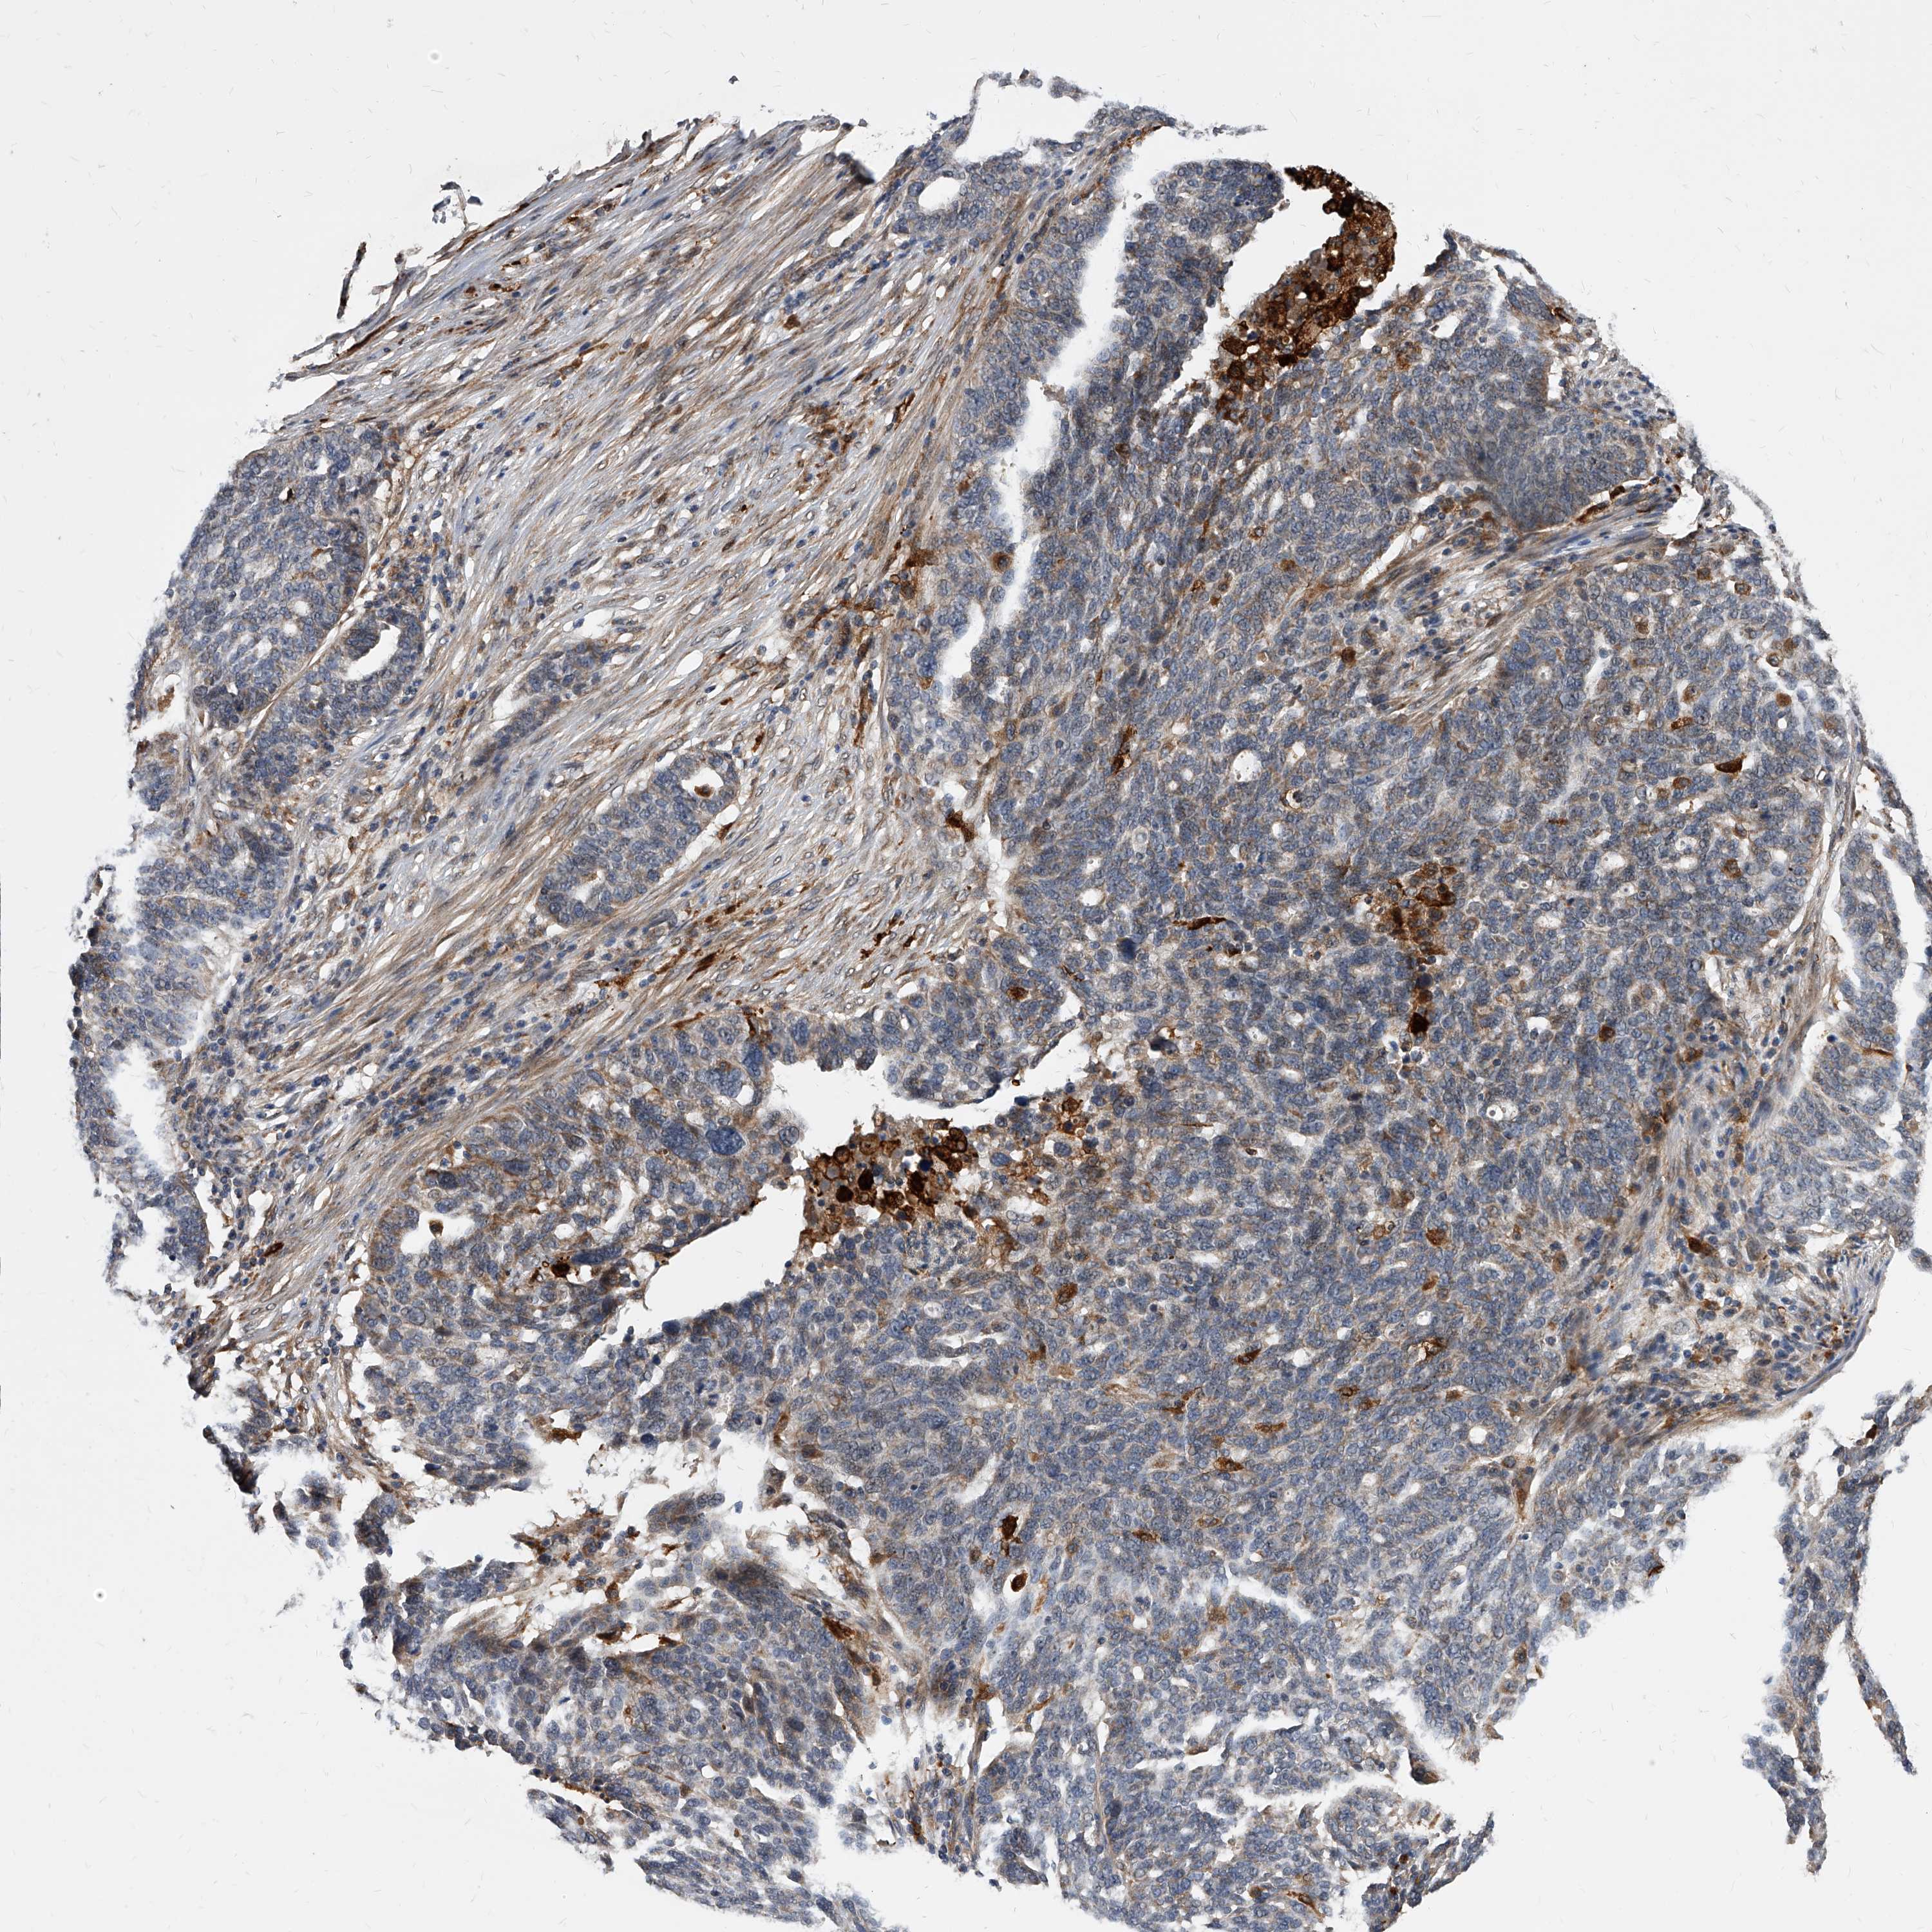

OVARIAN CANCER - Protein expressioni

A mouse-over function shows sample information and annotation data. Click on an image to view it in a full screen mode. Samples can be filtered based on level of antibody staining by selecting one or several of the following categories: high, medium, low and not detected. The assay and annotation is described here.

Note that samples used for immunohistochemistry by the Human Protein Atlas do not correspond to samples in the TCGA dataset.

Antibody stainingi

Antibody staining in the annotated cell types in the current human tissue is reported as not detected, low, medium, or high, based on conventional immunohistochemistry profiling in selected tissues. This score is based on the combination of the staining intensity and fraction of stained cells.

Each image is clickable and will lead to virtual microscopy that enables deeper exploration of all samples and also displays staining intensity scores, fraction scores and subcellular localization as well as patient and tissue information for each sample.

Antibody HPA029242

Cystadenocarcinoma, serous, NOS

Carcinoma, endometroid

Cystadenocarcinoma, mucinous, NOS

Carcinoma, NOS